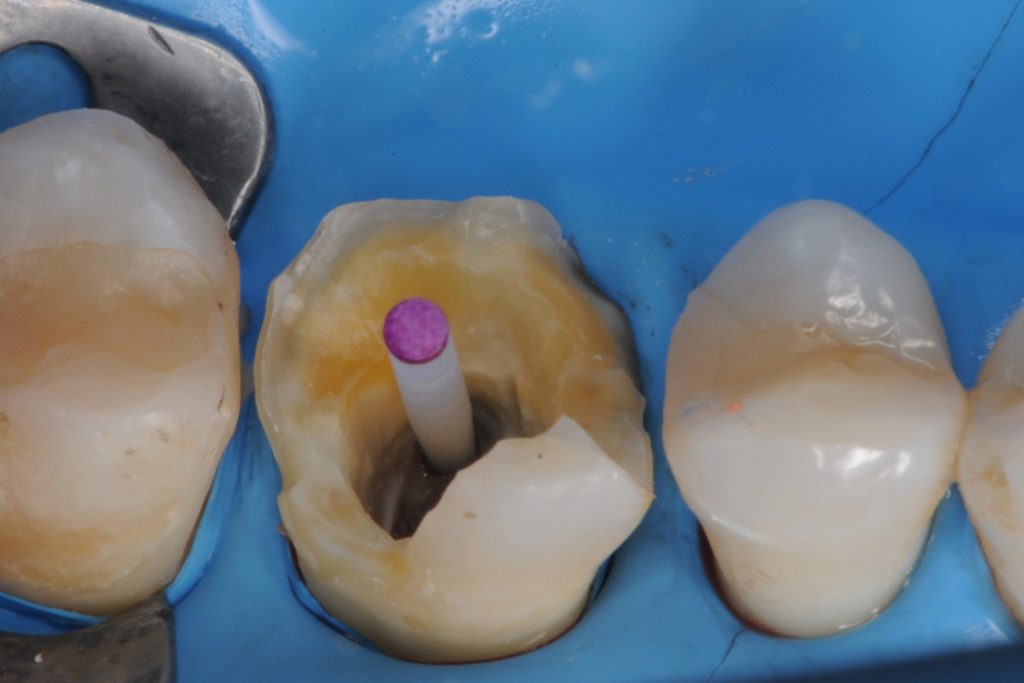

Фото 5. Після переліковування кореневого каналу в піднебінному корені було

сформовано простір для штифта, потім ми підібрали та встановили волоконний

штифт (LuxaPost від DMG) відповідного розміру. Не варто забувати, що нам треба

видалити тільки гутаперчу й герметик без препарування здорової тканини, тому що

її видалення тільки ослабить зуб. Ми не надаємо каналові форму, яка відповідає

формі штифта. Нам потрібно підібрати штифт, що відповідає формі того каналу,

над яким ми працюємо.